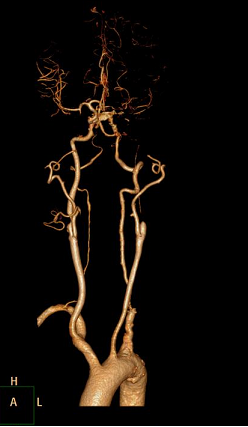

这是一位64岁的老年男性患者,反复头晕4年,症状最重时不能下床行走,严重影响日常生活,在当地医院定期输液治疗,仍无法减轻症状。2周前,症状明显加重,头晕发作频繁,站立即出现头晕加重,终日卧床,非常痛苦,输液治疗不能缓解。在当地医院行头颅SCT提示多发脑梗死,行颈部血管检查提示颅外动脉多发硬化、狭窄性病变。经多方打听,患者来到了郑大五附院血管外科住院治疗,颈部及头颅CTA提示颅外动脉多发硬化性病变,其中右颈动脉重度狭窄,左颈动脉、右椎动脉纤细,近似闭塞,左椎动脉开口处重度狭窄,左侧颅内动脉烟雾病样表现,供应颅脑血供的4支重要血管都不同程度地出了问题,且左侧颅内血管也存在问题,这说明颅脑严重缺血,随时可能发生脑梗死、脑血栓等致命性危害,治疗刻不容缓!但所有的血管又不可能同时处理,那究竟先处理哪一支呢?而哪些动脉是不需要处理的呢?开通颅外血管后对颅内动脉的影响有多大,患者脆弱的大脑能不能承受呢?一系列问题摆在了医生面前。在王兵副院长的带领下,血管外科全体医师进行了激烈的讨论,为患者制定了一个可行的治疗方案,由于左颈内动脉及右椎动脉纤细,开通对患者颅内血供的意义不大,所以可后期处理,右颈动脉和左椎动脉开通的意义较大,结合患者症状优先开通供应前循环的右颈动脉更为妥当,且患者左颅脑动脉烟雾病样表现,所以开通右颈动脉导致脑出血的风险较小,由于多支病变,为了避免阻断导致脑梗死风险,手术方式选为支架置入术理所当然,但右颈动脉的斑块性质不良,存在溃疡斑块可能,一旦溃疡斑块被支架挤碎就会发生右侧大脑半球的栓塞事件发生,所以对腔内的操作技巧要求极高。这就相当于在一个摇摇欲坠的房屋中加支撑柱,搞不好就会因为操作不当造成房屋的彻底坍塌。但王兵副院长带领的团队对此信心满满,这种自信来源于丰富的临床经验、恰当的治疗策略、高超的手术技巧和来自患者的绝对信任。

术前CTA